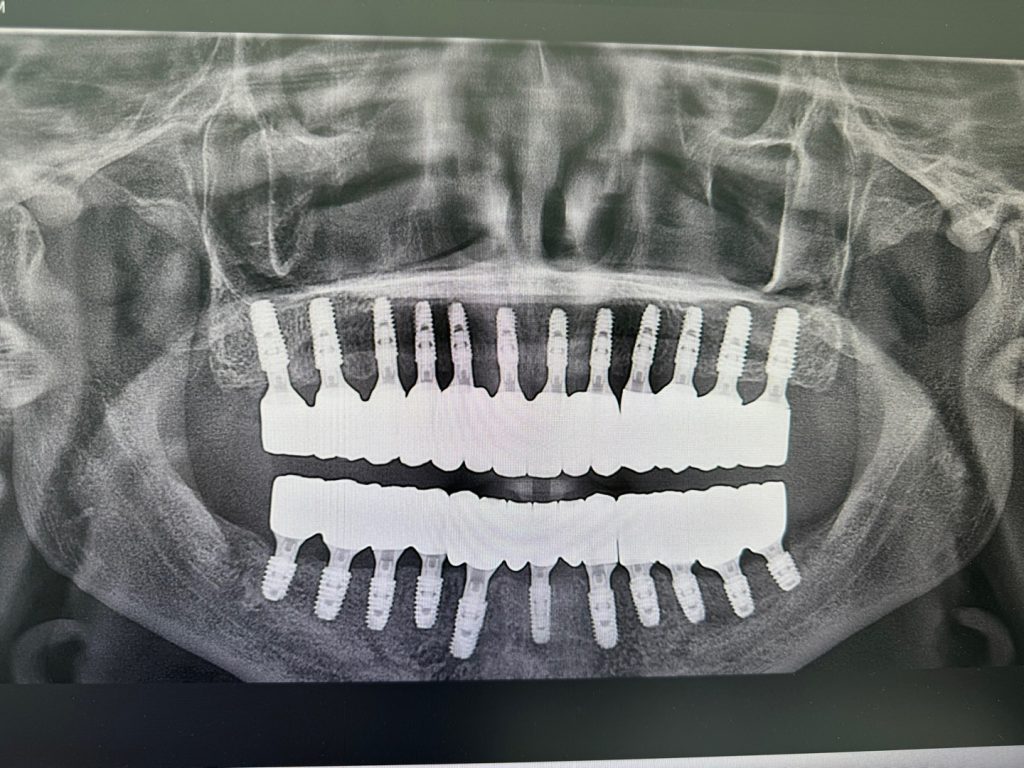

몇 개월에 걸친 치료가 다 마쳤습니다. 결론적으로 얘기하면 부평치과 중에서는 플란치과 부평을 가장 추천할 수 있을 것 같습니다. 이유는 아래 이미지를 보시면 느낌이 오실 겁니다.

아래 사진은 치료 결과 얘기 들으면서 엑스레이 화면 찍은 겁니다.

치과에 무지한 저도 엑스레이 보고 경악했습니다. 어찌나 이쁘게 가지런히 심으셨는지.. 다 그런가 싶어서 처음 플란치과병원 부평점을 소개해 준 지인에게 엑스레이 사진 보내주니 ‘미쳤다’는 반응이더군요.

자기 지인들한테도 돌렸는데 경력 25년 이상 치위생사분도 이렇게 잘 심은건 처음 본다는 반응이었다는군요. 부평치과 추천해 준 친구에게는 너무 고맙다는 얘기와 함께 소고기 한 번 쏘기로 했습니다.